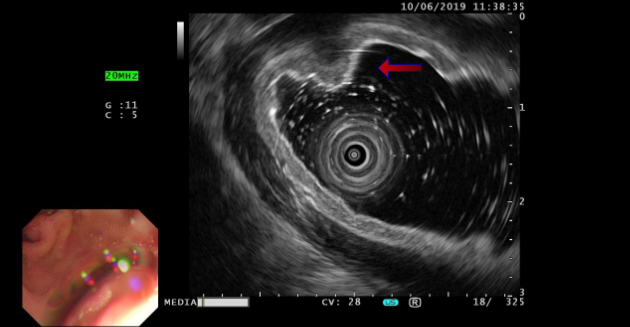

In 2019, ultrasound endoscopy still indicated a submucosal bulging mass on the lesser curvature of the gastric antrum, and submucosal ectopic pancreas was considered. (Figure 2).